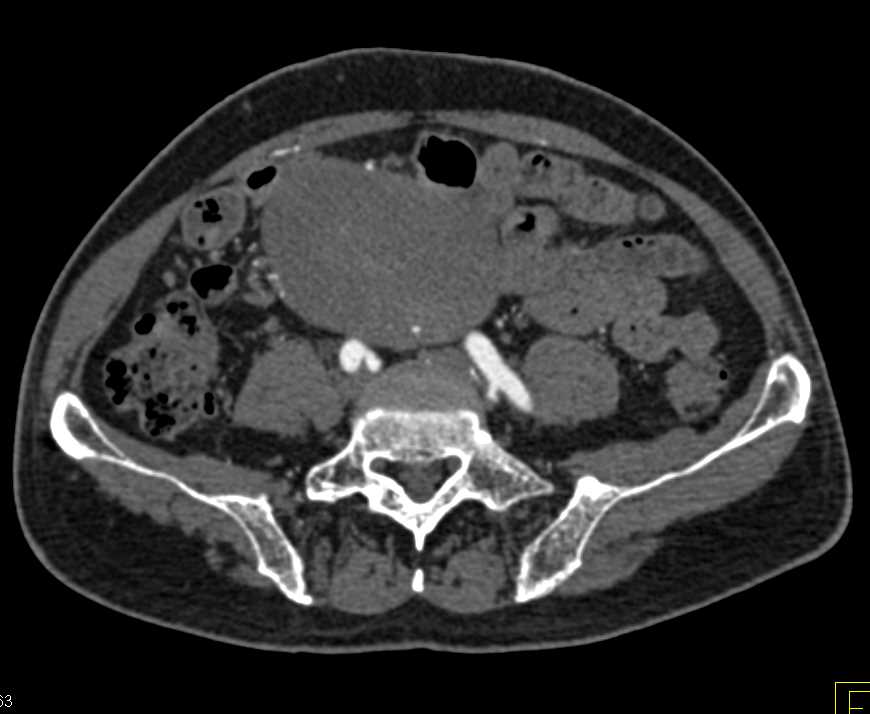

Carcinoid Tumor in the Terminal Ileum